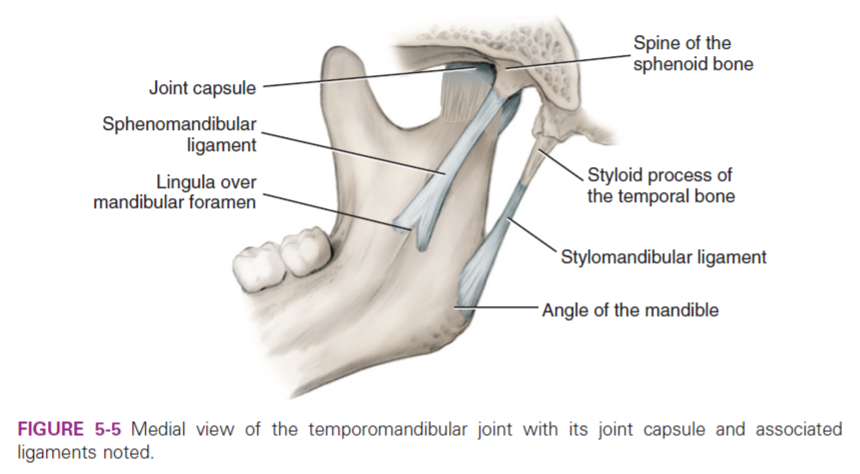

Ligament

- Stylomandibular ligaments

- Sphenomandibular ligaments

Info

Stylomandibular ligament 分隔 parotid ,submandibular g.